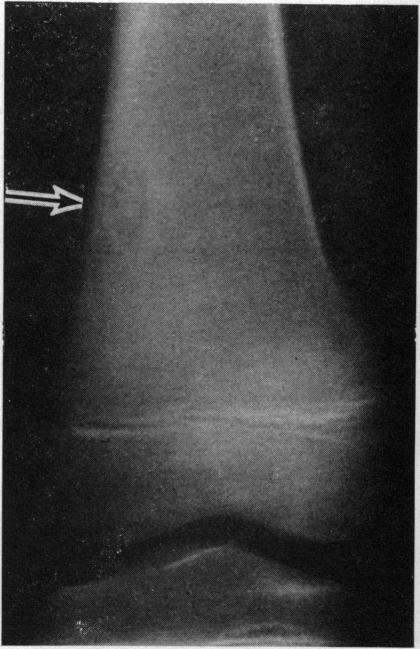

The various types of primary tumour that may affect the bones are reviewed. No attempt is made to cover so wide a field in detail, but the more important clinical, radiological, and histological features of each type of tumour are emphasized and its management outlined. Mention is also made of a number of lesions which, while not strictly tumours, may resemble them radiologically.